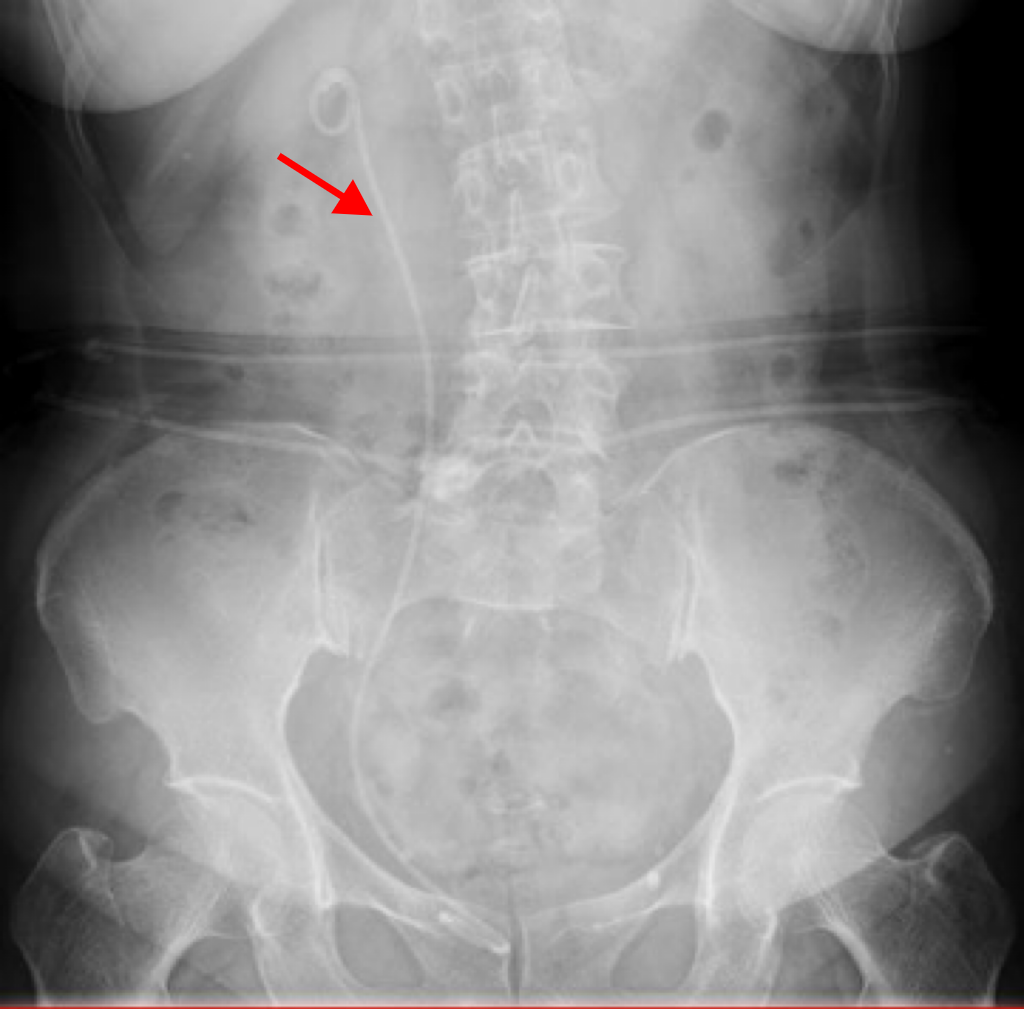

患者入院行腹部CT检查。发现右肾结石,大小约2.0cm

患者术后第二天复查

未见明显结石